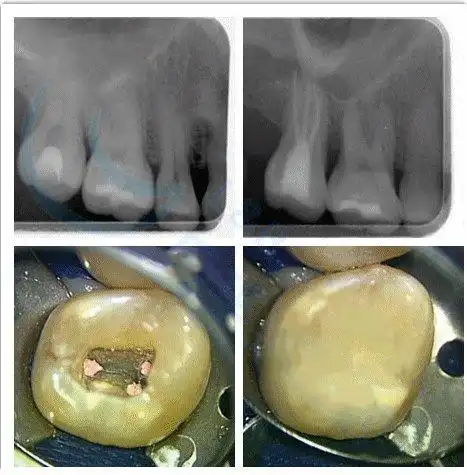

治疗各类儿童龋齿,根尖周病,儿童牙齿保护性治疗,乳牙涂氟,小儿窝沟